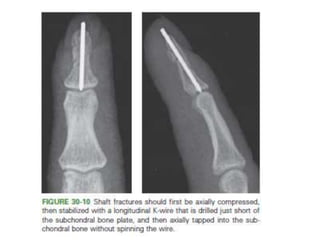

• For short oblique and transverse fractures,

– longitudinal K-wires .

Closed Reduction +Internal Fixation. • Reducible but unstable isolated fractures. • For long oblique and spiral fractures – three K-wires- perpendicular to the fracture • For neck fractures- – retrograde pinning may be necessary • For short oblique and transverse fractures, – longitudinal K-wires .